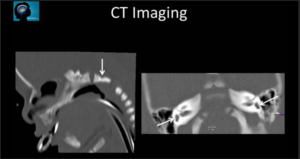

A 3-year-old child is admitted to the hospital due to decreased appetite and weight loss. She has been afebrile, and has not had vomiting or diarrhea.

Her activity level has decreased over the past two weeks.

She had been healthy until 2 months ago, when she was hospitalized for 48 ...

infection with mild respiratory distress and poor fluid intake.